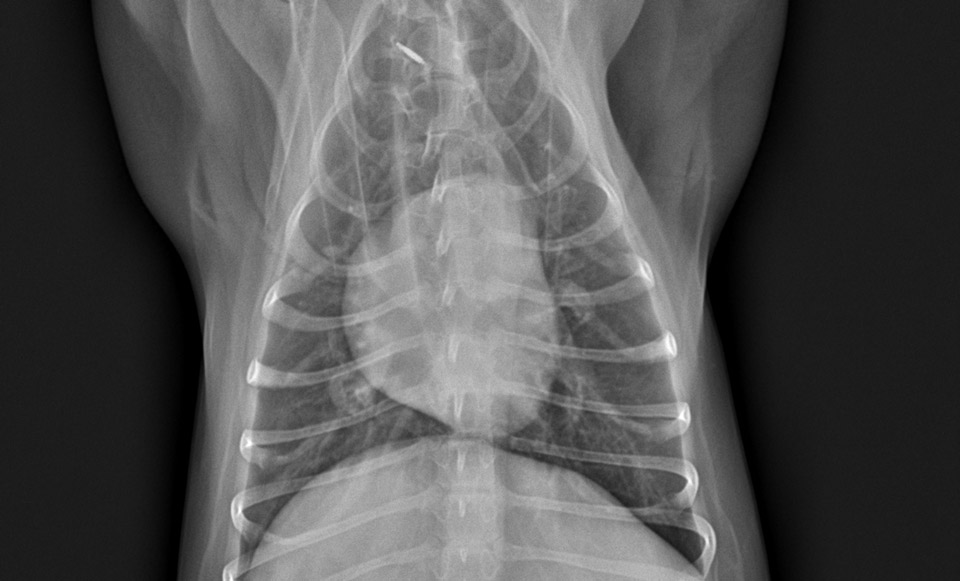

초기던 중기던, 이미 심장사상충 감염은 참깨의 심장에 변화를 이미 주었습니다.

이미 참깨의 심장이 한쪽이 다른 쪽에 비해서 비대해 졌습니다.